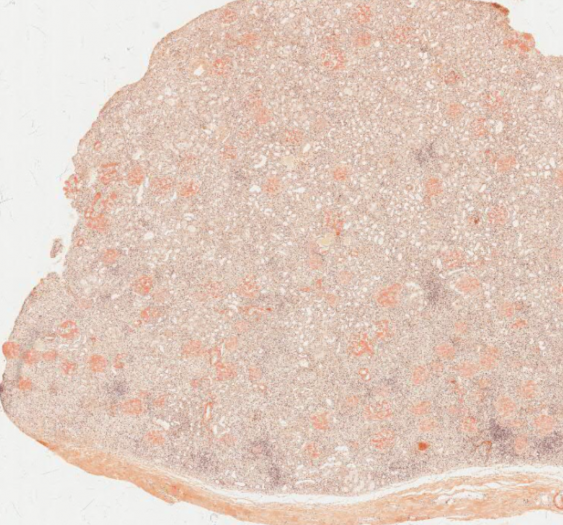

细胞和组织的适应与损伤

肝脂肪变性(甘油三酯)(AP016)

肝脂肪变性(甘油三酯)